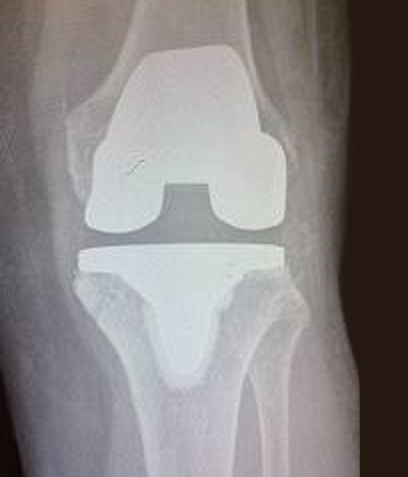

איכות חיים. ברך עם תותב (צילום אחרי הניתוח באדיבות ד"ר בנימין בנדר)

הטיפול הניתוחי כרוך בהחלפת מפרק הברך בתותב. הניתוח מאפשר שיפור ניכר באיכות החיים. הטכניקות החדשניות והשתלים המודרניים מאפשרים חזרה מהירה וקלה יחסית לשגרת היום יום, כולל עבודה והתעמלות.